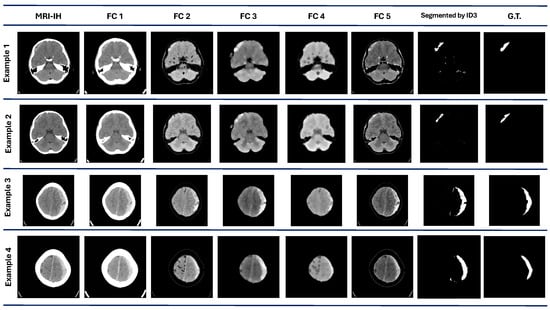

Finally, in the MRI-IH, the algorithm performance achieves a mean and median value of 0.44 and 0.43, respectively. This dataset was the most challenging part of the proposal. The best value achieved is the lowest compared to the other datasets, with only a 0.56 DICE value. Also, it has the second-lowest value for the worst performance in the different datasets. The visual results with this dataset are shown in Figure 5. In example 1, the segmentation results show some regions marked as ROI, according to the G.T. Examples 3 and 4 show a good visual performance. However, some regions are discarded and include areas that do not correspond to the ROI.

Figure 5.

MRI-IH dataset results. The first column contains the original images. are the images processed by each best individual for each evolved population. The ID3 column contains the images segmented by the model at the pixel level. The G.T. column contains objective images.

The significant variability is present in the DRIVE dataset, where some outliers exist and correspond to the worst and lowest values. As we can observe in Figure 3, the MRI-IH dataset reflects the difficulty for our method to perform the segmentation, where the ROIs are small regions that are hard to segment.